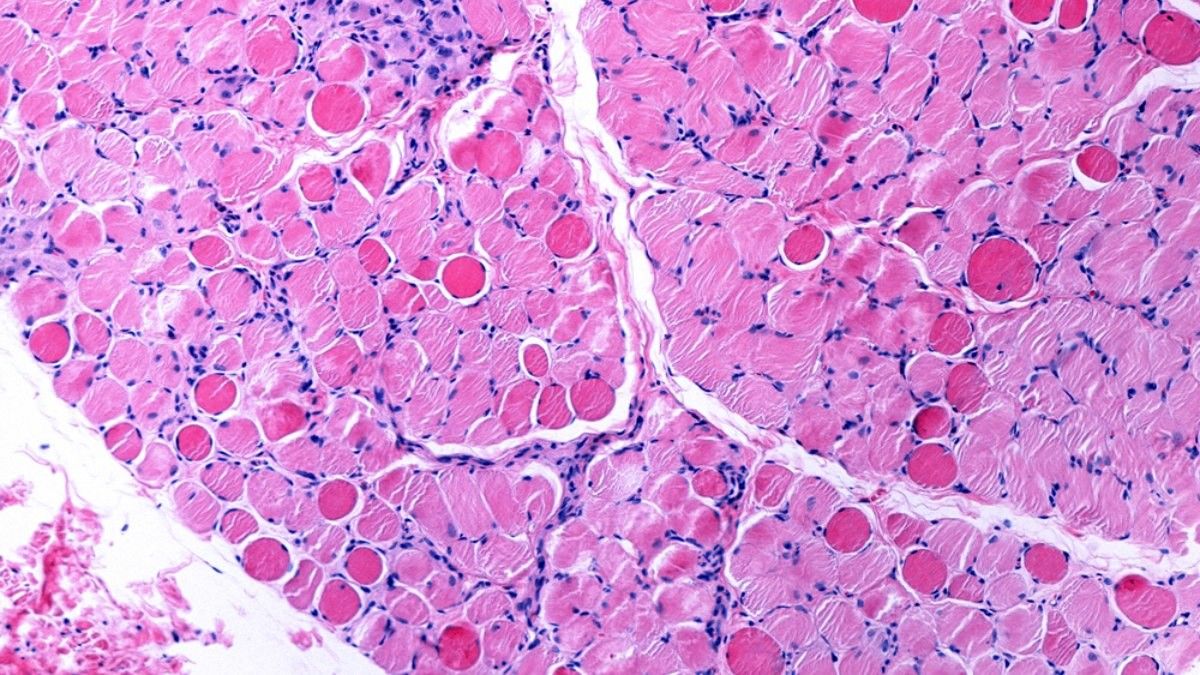

3. Duchenne Muscular Dystrophy (DMD)

Penyakit langka ini dapat memengaruhi penggunaan otot sukarela atau otot lurik dalam tubuh.

Kondisi ini umumnya lebih banyak memengaruhi bayi laki-laki. Namun, tidak menutup kemungkinan bahwa bayi perempuan juga bisa mengalaminya.

Dalam tahap awal (usia 2 sampai 6 tahun), anak akan mengalami kesulitan berjalan, berlari, atau memanjat. Bahkan, beberapa di antaranya kesulitan untuk mengangkat kepalanya sendiri.

Pada akhirnya, otot pernapasan akan terganggu dan menyebabkan si kecil sulit bernapas, kelelahan, atau jantung membesar.